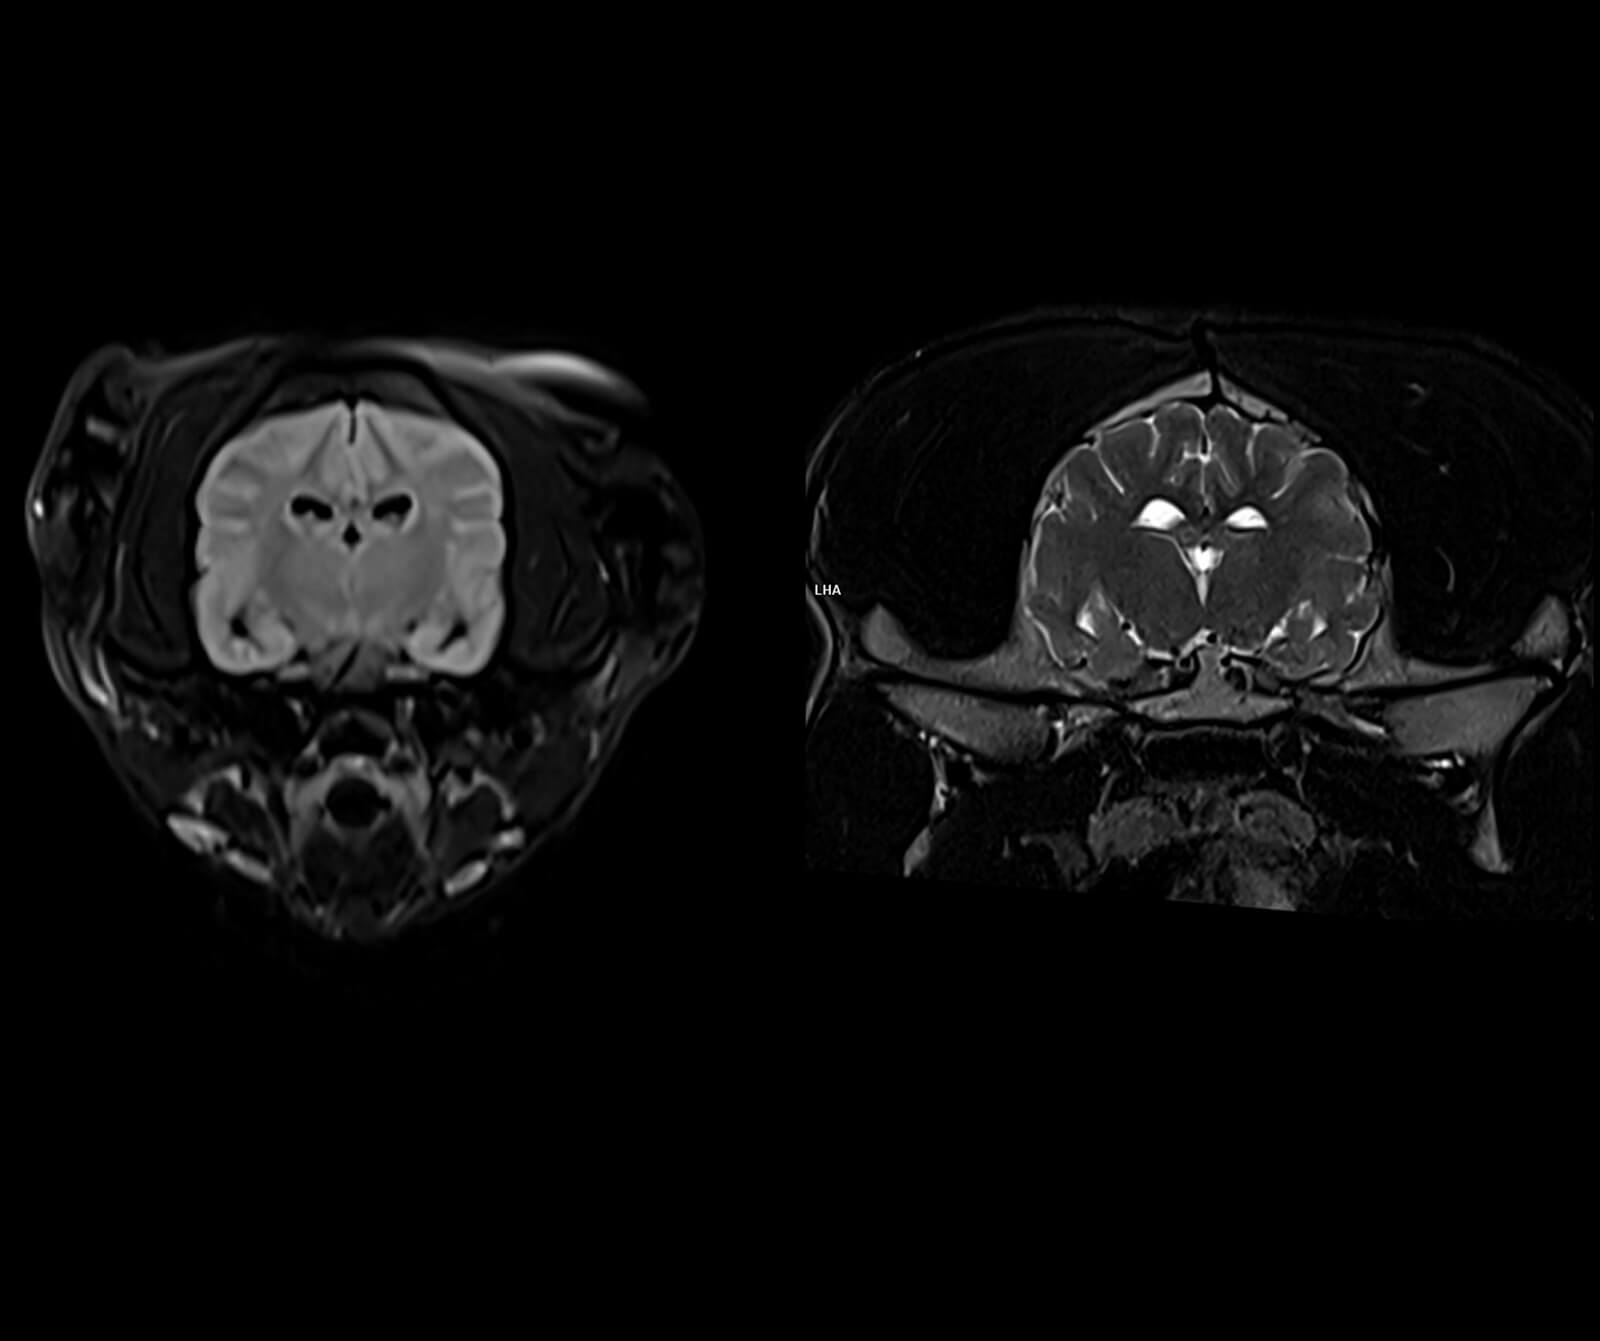

Manyetik Rezonans Görüntüleme (MR), sevimli dostlarımızın vücudundaki doku ve organların yüksek çözünürlükte, ayrıntılı ve güvenli biçimde değerlendirilmesini sağlayan ileri düzey bir tanısal görüntüleme yöntemidir. Radyasyon içermeyen bu yöntem, özellikle yumuşak dokuların detaylı incelenmesi gereken durumlarda en değerli tanı araçlarından biridir.

Veteriner hekimliğinde MR; beyin, omurilik, sinir sistemi, kas-iskelet sistemi ve iç organ hastalıklarının değerlendirilmesinde kritik rol oynar. Kemik yapılar dâhil olmak üzere vücudun tüm bölgeleri MR ile ayrıntılı şekilde incelenebilir.

• Beyin ve nörolojik hastalıkların değerlendirilmesi

• Spinal kord incelemeleri

• Göz hastalıkları